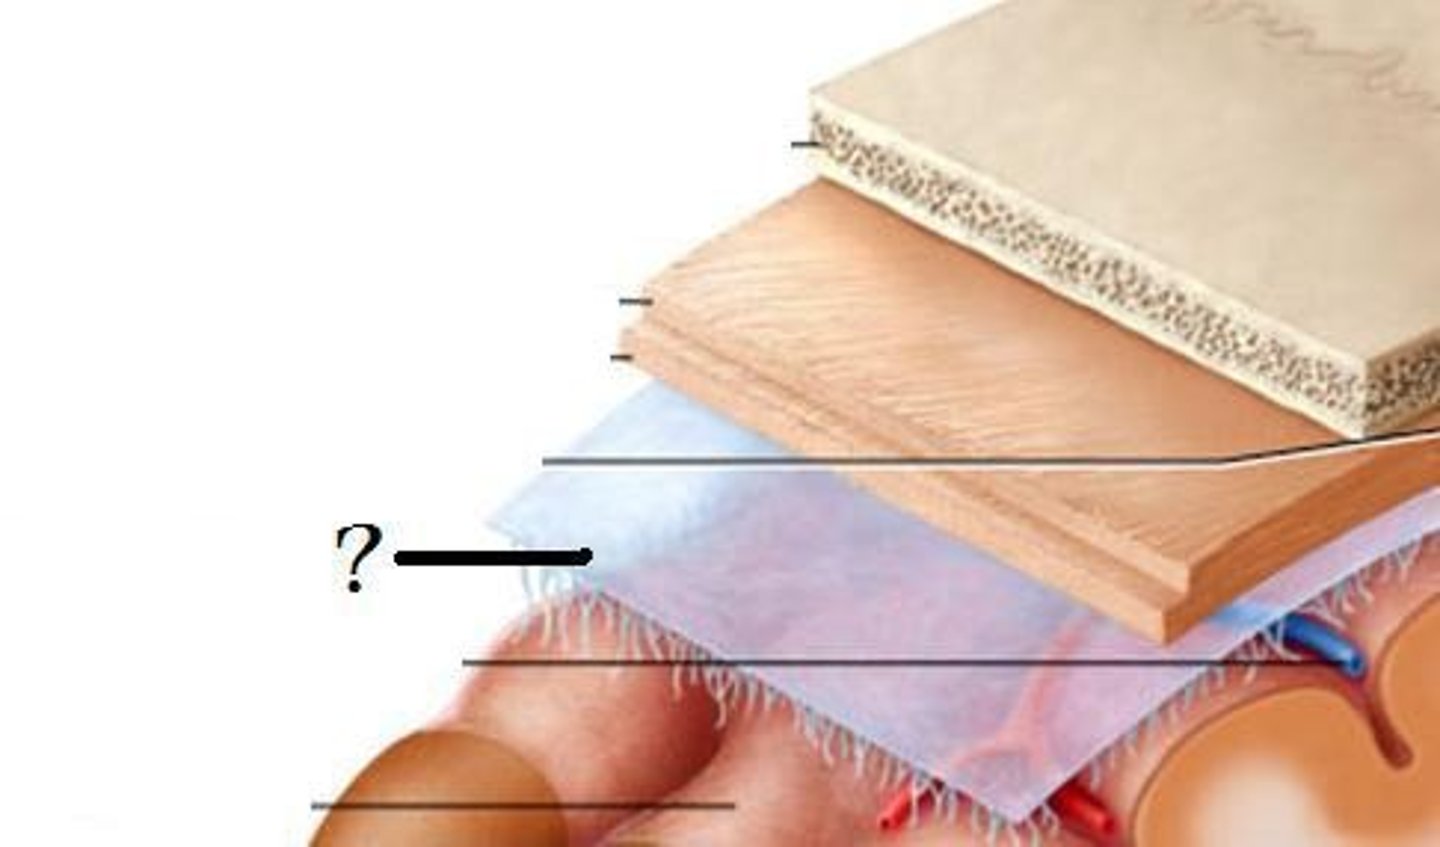

meninges

•Three connective tissue layers

•Separate and support soft tissue of brain

•Enclose and protect blood vessels supplying the brain

•Help contain and circulate cerebrospinal fluid

•From deep to superficial (PAD to protect the brain)

--Pia mater

--Arachnoid mater

--Dura mater

dura mater (brain)

thick, outermost layer of the meninges surrounding and protecting the brain and spinal cord

arachnoid mater (brain)

middle web-like layer of the meninges

pia mater (brain)

thin, delicate inner membrane of the meninges

spinal meninges

dura mater, arachnoid mater, pia mater (PAD to protect the spinal cord from deep to superficial)

dura mater (spinal cord)

thick, outermost layer of the meninges; 5 on image

arachnoid mater (spinal cord)

middle weblike layer of the meninges; 4 on image

pia mater (spinal cord)

thin, delicate inner membrane of the meninges; 3 on image